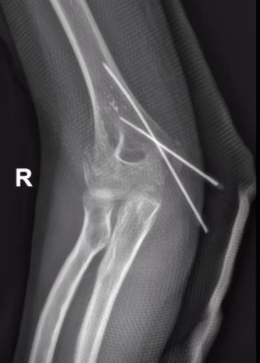

有些疼痛难以用语言形容您是否经历过这样的困扰?✦ 拧毛巾时手腕传来一阵刺痛✦ 拿筷子时手指突然发麻无力✦ 连简单的抓握动作都变得困难异常...近日,日照市康复医院就来了这样一位患者——从事手工劳作十余...